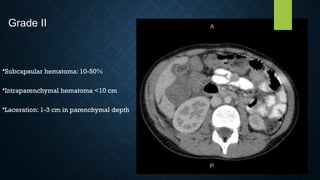

GRADE II

• Subcapsular hematoma 10-50%

• Parenchymal hematoma <5 cm

• Laceration 1-3 cm depth